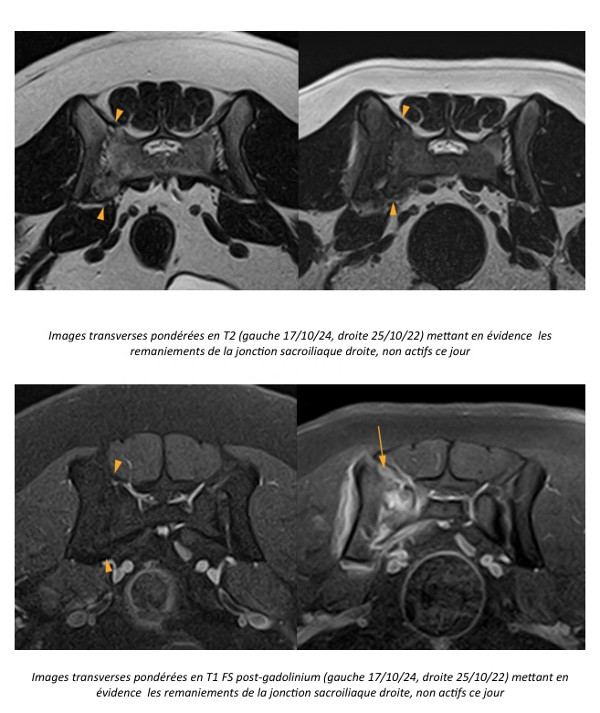

Figure 1

Figure 2